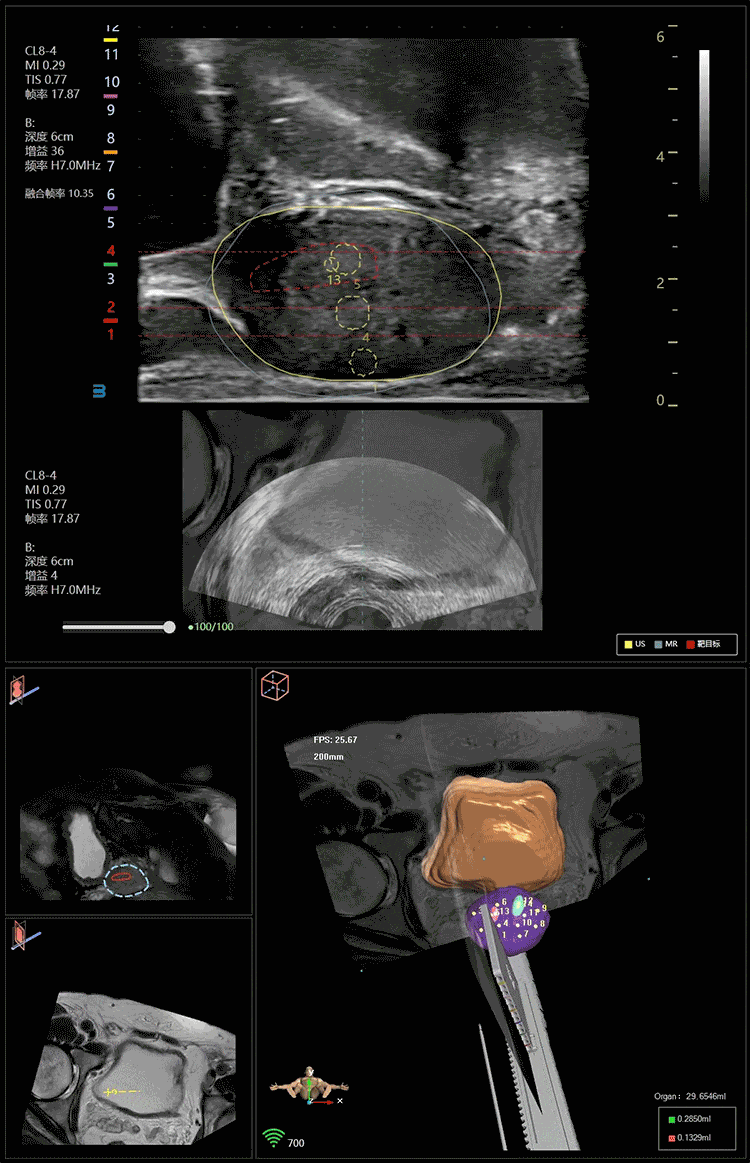

VENUS支持MRI/CT/PET与超声等不同影像数据,通过AI技术智能配准及分割器官图像,将不同模态图像融合精度提升至1毫米的高标准,三维影像重建技术快速构建3D人体解剖结构模型,帮助术者从可视化的手术视野中快速定位病灶,辅助规划手术路径和术中动态引导穿刺等介入操作。

VENUS定制化设计了前列腺、肾脏等器官专用程序,精准匹配不同术式需求。目前,VENUS协助全球700余家医院高效完成了累计超过9000例手术,覆盖前列腺穿刺活检、经皮肾镜碎石取石术(PCNL)、前列腺增生热蒸汽消融、前列腺癌局灶治疗等高难度泌尿系统疾病诊疗。